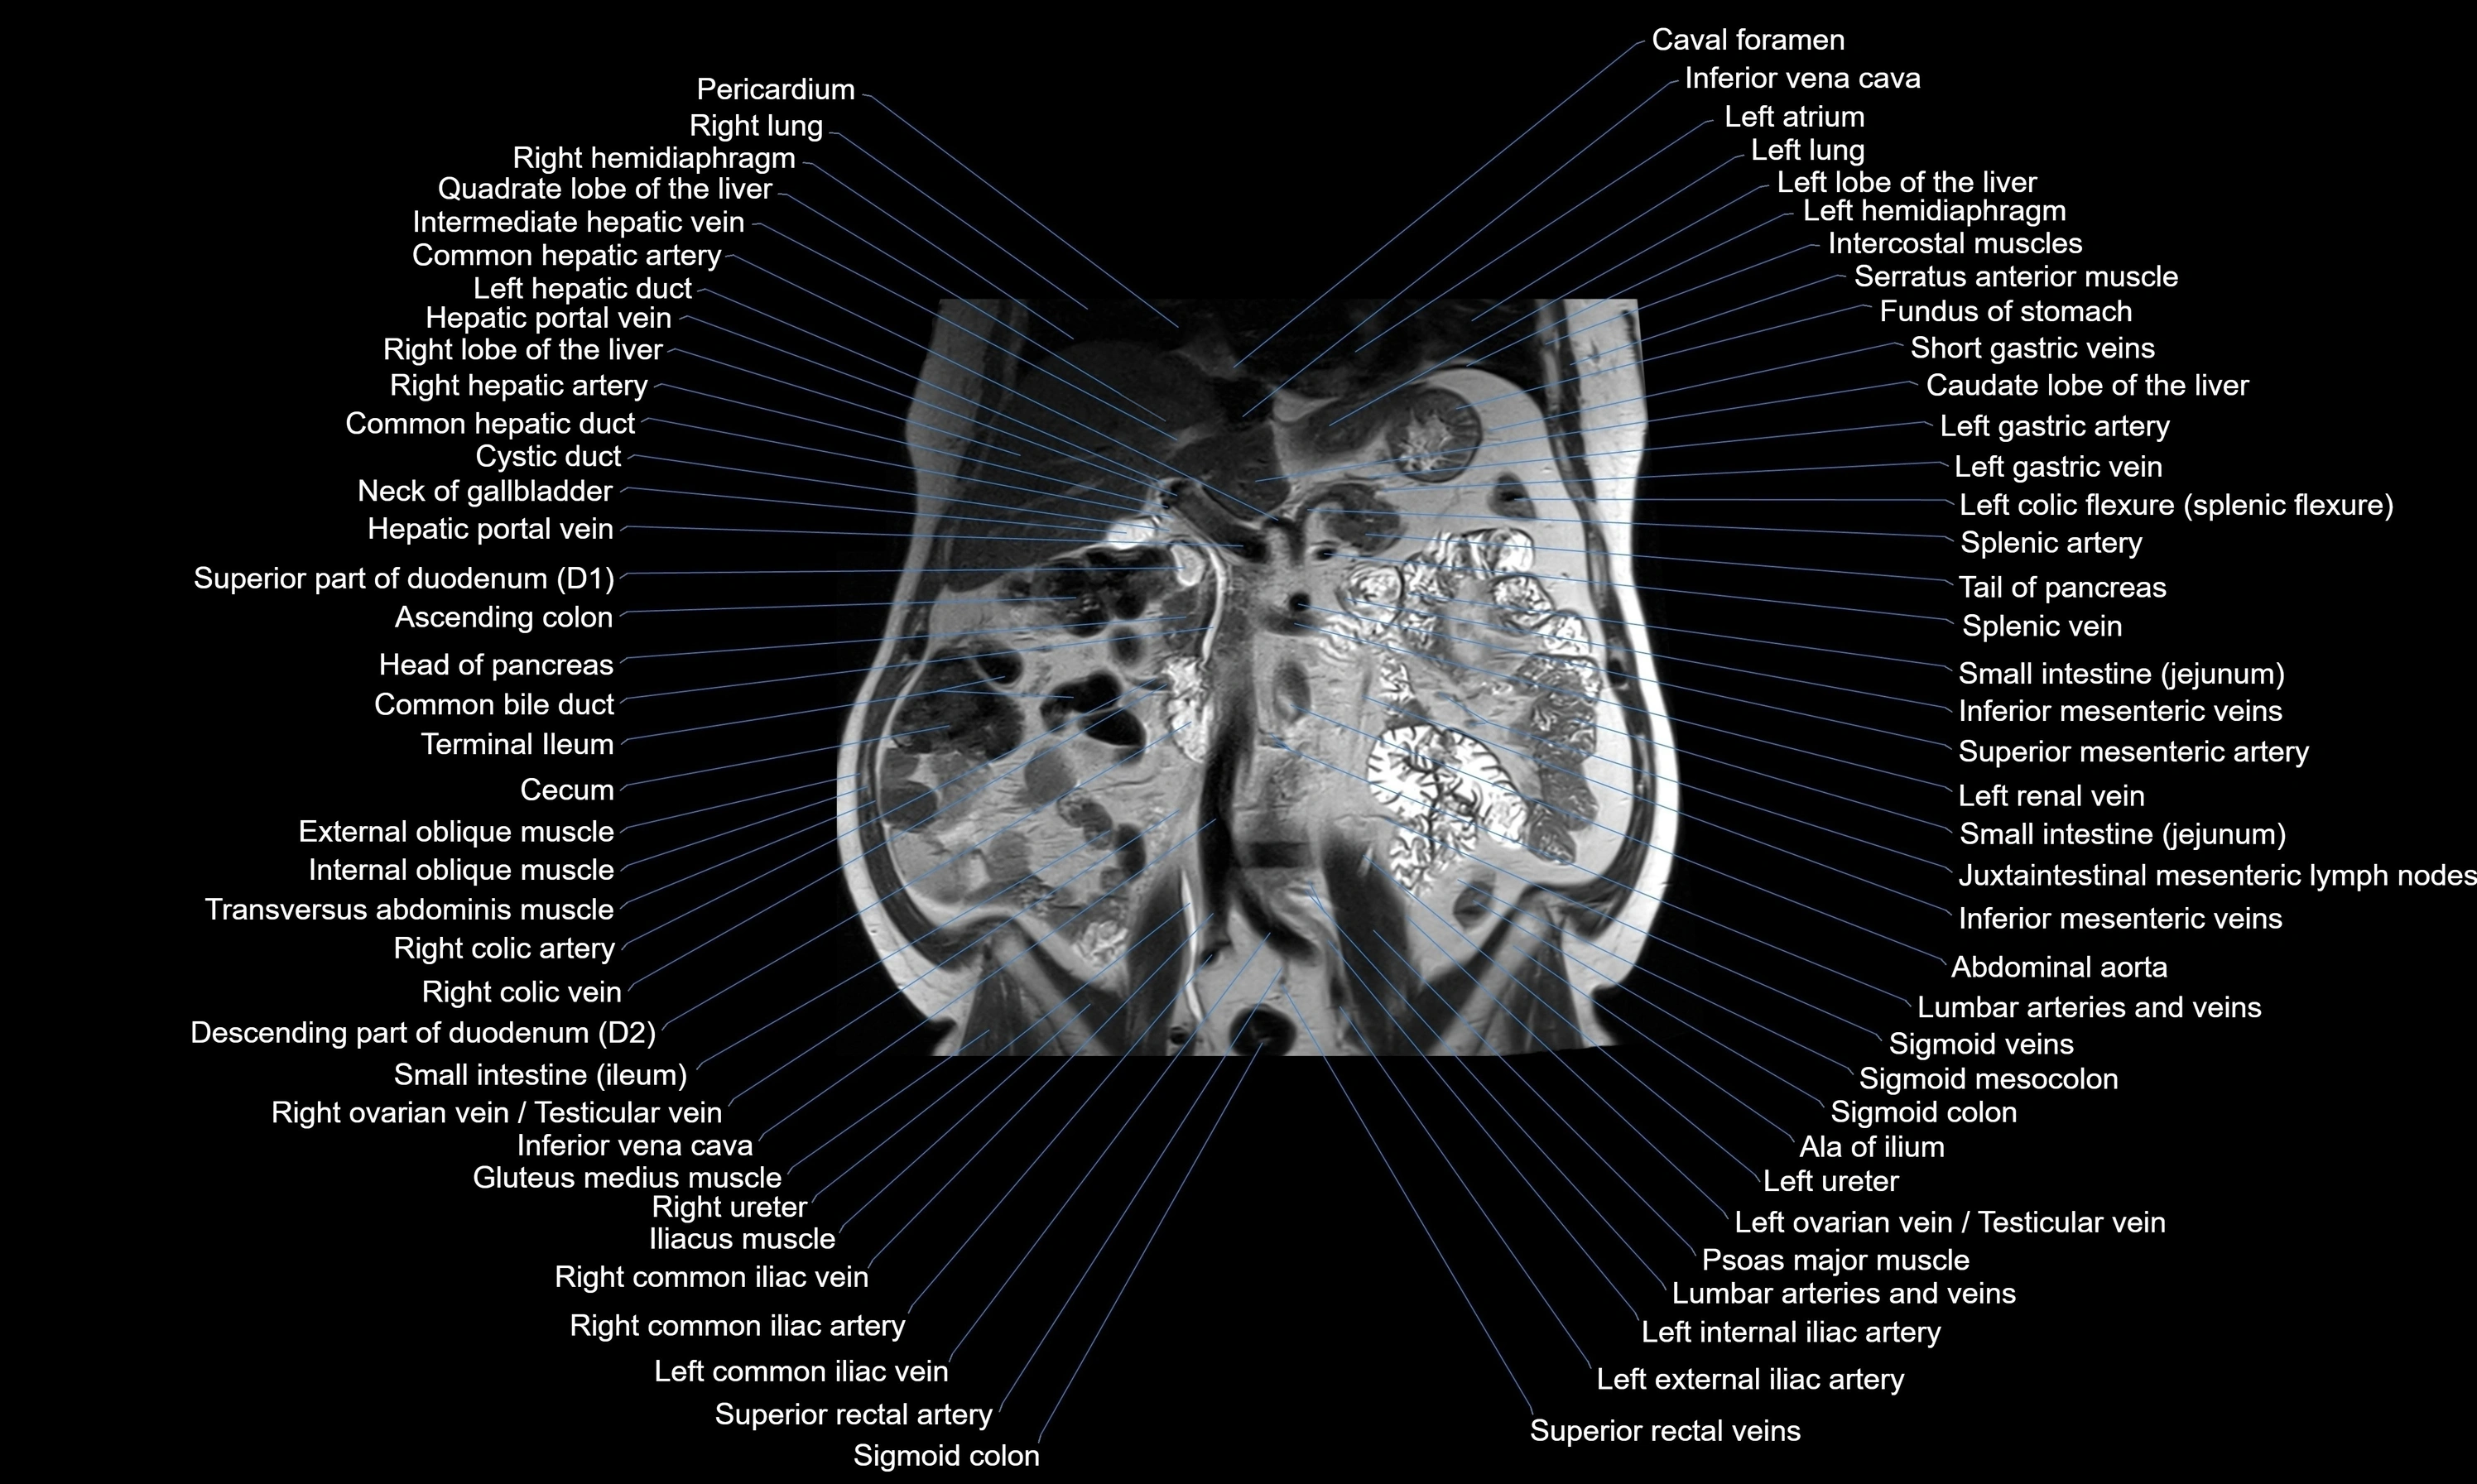

- Abdominal aorta

- Ascending colon

- Cecum

- Common bile duct

- Common hepatic artery

- Common hepatic duct

- Cystic duct

- Duodenum – Descending part (D2)

- Head of pancreas

- Hepatic portal vein

- Inferior mesenteric artery (IMA)

- Inferior mesenteric vein

- Inferior vena cava

- Internal oblique muscle

- Left atrium

- Left colic flexure (splenic flexure)

- Left hemidiaphragm

- Left lobe of liver

- Left renal vein

- Left ureter

- Marginal artery of Drummond

- Psoas major muscle

- Right colic flexure (hepatic flexure)

- Sigmoid veins

- Splenic artery

- Superior mesenteric artery (SMA)

- Superior rectal artery

- Tail of pancreas

- Terminal ileum

- Transverse colon

- Transverse mesocolon